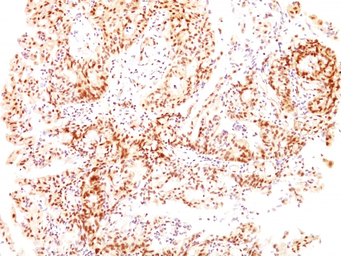

IHC-P analysis of human ovarian carcinoma tissue using GTX34712 Estrogen Receptor beta antibody [ESR2/686].

IHC-P analysis of human breast carcinoma tissue using GTX34712 Estrogen Receptor beta antibody [ESR2/686].

IHC-P analysis of human bladder carcinoma tissue using GTX34712 Estrogen Receptor beta antibody [ESR2/686].

IHC-P analysis of human gastric carcinoma tissue using GTX34712 Estrogen Receptor beta antibody [ESR2/686].